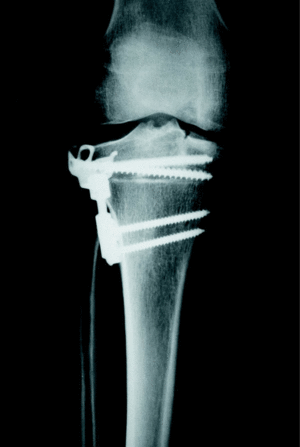

Figura 3. Corrección quirúrgica del caso mostrado en la figura 2. Se utilizó la placa T3, que proporcionó un montaje estable después de la osteotomía, añadiéndose un tornillo de compresión para mayor solidez. La corrección fue de 8o de valgo; la consolidación se obtuvo a las 9 semanas. La imagen corresponde al control a los tres años.

La consolidación de la osteotomía tibial se logró a las 9,7 +/ 1,25 semanas (mínimo: 8; máximo: 12) (figs. 2 y 3). En el postoperatorio inmediato se presentaron 6 complicaciones. En 4 pacientes existió una paresia transitoria del ciático poplíteo externo que se recuperó en todos ellos a las 9 semanas de media. Hubo un caso de infección superficial, que curó con tratamiento antibioterápico oral y curas tópicas; y un caso de fractura de platillo tibial interno por osteotomía insuficiente, que condicionó un mal resultado (fig. 4). A medio plazo hubo dos pacientes que precisaron la retirada de la placa por molestias atribuidas a la protrusión subcutánea del material.

El seguimiento radiológico final demostró una corrección del eje de la extremidad que pasó a ser de 8o de valgo (desviación estándar [DE]: 2,2) (mínimo: 5; máximo: 12). No hubo cambios entre la corrección apreciada en el postoperatorio y la final, no progresó la usura ni el pinzamiento de la interlínea interna, ni evolucionó la artrosis en los otros compartimentos. Los resultados de la evolución clínica y radiológica al final del seguimiento se muestran en la tabla 1.